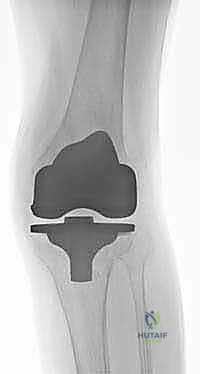

| نوع المفصل المستخدم | مفصل قياسي سطحي. | مفصل مراجعة مع سيقان معدنية (Stems) ودعامات. |

2. الدعامات المعدنية (Metal Augments / Blocks)

عندما يكون الفقدان العظمي متوسطاً (من 5 إلى 15 ملم) ومحصوراً في جانب واحد أو جانبين من قصبة الساق، يتم استخدام كتل أو أسافين معدنية (مصنوعة من التيتانيوم أو الكروم كوبالت). يتم تثبيت هذه الدعامات بمسامير أو إسمنت في الجزء السفلي من صينية المفصل الصناعي لتعويض الارتفاع المفقود واستعادة الاستواء الميكانيكي للركبة.